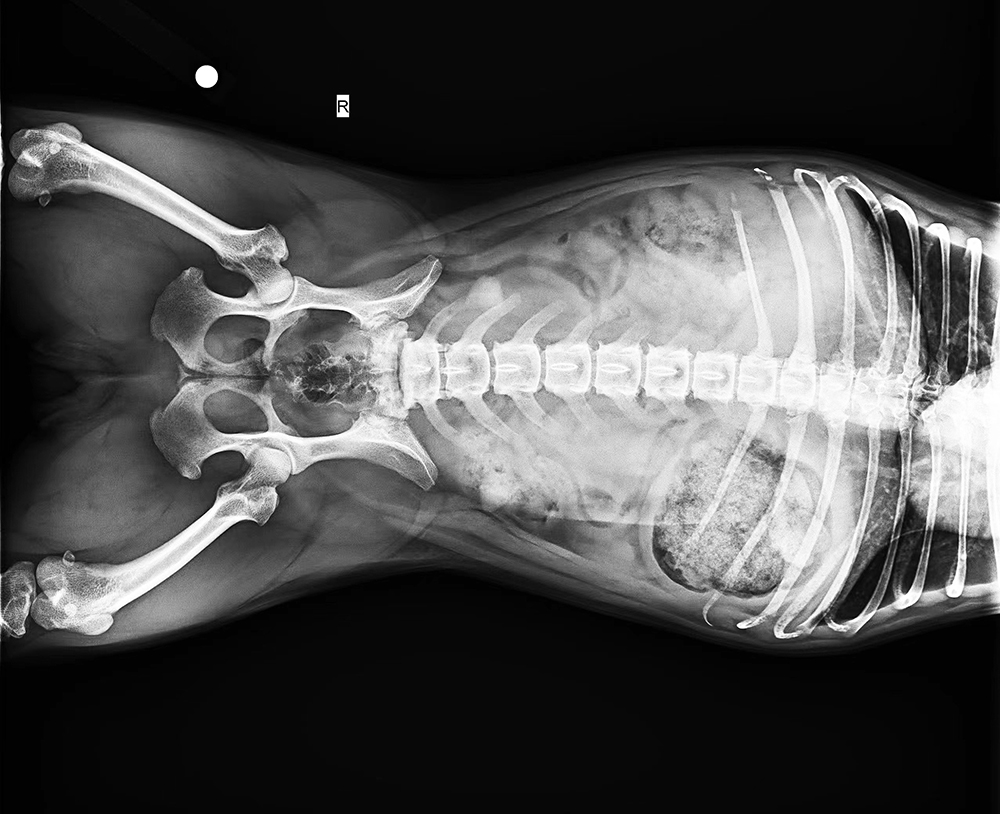

“宠物看病比人看病贵”、“费用不合理”、“过度医疗”......宠物医疗总是饱受争议。据报道,中国城镇养宠用户已超过7000万人,宠物犬猫的数量已经超过1亿只。《中国宠物行业白皮书——2022年中国宠物消费报告》显示,在国内,宠物主花在狗身上的年平均消费大约是2882元,花在猫身上的年平均消费大约是1883元。在宠物的主要消费市场中,医疗排在食品之后,市场份额为29.1%。在医疗之中,诊疗占比最大,其次才是药品、体检和疫苗。

近些年,中医也被应用在了宠物身上。让我们跟随摄影师的镜头,走进宠物诊疗室,一探宠物的看病故事。